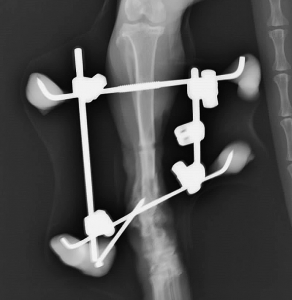

下のレントゲン写真は手術8か月目のものです。通常の単純な骨折ならば既に完治している期間です。骨折は冬でしたが、固定を外すのが夏になってしまいました。ほぼ同時に手術したもう一か所の上腕骨骨折はプレートによる内固定で手術2か月弱で治療を終えていることを考えると非常に長い治療期間でした。

長期間かけてようやく少しづつ仮骨形成(骨がくっつき始めること)し始めましたので、レジンを除去して5本あった金属ピンを3本に減らした写真です。こうすることで徐々に骨に負荷をかけていきます。